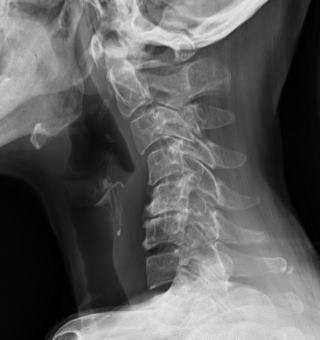

診断は神経学的診察に加えてレントゲン撮影(6R、正側面、両斜位、前後屈)で評価を行い、神経や椎間板などの軟部組織の評価はMRIで行います。

画像診断

頚椎単純レントゲン撮影、MRI、CTが有効です。骨棘などの変性所見は、必ずしも臨床症状と一致せず、無症候性のこともあります。画像所見が臨床症状と合致する可動か慎重に判断します。

・単純レントゲン撮影:椎間板腔狭小、Luschka関節や椎間関節の変性、骨棘 椎間孔の骨性狭窄は斜位像で描出されやすいですが、斜位像(50-55度)で椎間孔を旨く映し出すのは、なかなか難しく苦労します。(同側、対側と比較します)

・CT、MRI CTは骨の描出に優れ、MRIは軟部組織の描出に優れています。椎間孔の狭窄はMRIでの読影は難しいとされています。正確な診断には、いずれも3mm以下のスライスが必要とされています。神経根症状があるにも関わらず明確な所見が認められない場合は、斜位MRIや3D-MRIが有用であるとされています。